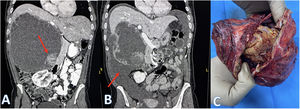

A 46-year-old woman with no medical history of interest was assessed at another centre for dyspepsia, precocious satiety and abdominal pain in the right abdomen, with no weight loss, asthenia, or anorexia. An abdominal CT scan was performed (Fig. 1A) where a lesion of 20.8 × 14.3 × 21.5 cm was observed with cystic and solid formations in the interior, along with septa and peripheral calcifications. Hydatidosis serology was negative. The patient was then referred to our centre for evaluation.

Four days after the initial visit, we were notified by the Emergency Department as the patient was suffering from extremely intense abdominal pain and symptoms of generalised defence. Lab tests showed no notable changes: CRP 0.47 mg/dl (0–1), ALT: 52 U/l (0–49) and GGT: 131 U/l (5–55). Abdominal CT scans showed a large amount of intra-abdominal free fluid (Fig. 1B).

In view of these findings, subcostal laparotomy was performed, locating 2200 c.c. of cloudy fluid; the patient’s microbiological study did not identify microorganisms, only leukocytes. The lesion had a necrotic area of 0.5 cm through which intracystic fluid was draining. A technically complex total cystectomy was performed due to its proximity to the right portal pedicle, but without any infiltration, as well as a cholecystectomy (Fig. 1C). The postoperative period passed without any major complications, undertaking a transfusion of concentrated red blood cells only (Clavien-Dindo II) and this was given on the 5th postoperative day.